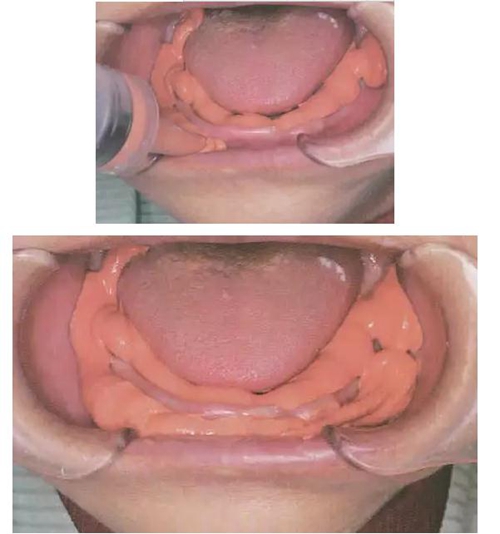

FCB專用托盤是阿部二郎大師的專利發(fā)明——使用FCB專用托盤獲得的初印模,可以保留磨牙后墊區(qū)變形最小的自然形態(tài),以最大限度獲得下頜磨牙后墊區(qū)吸附力!而傳統(tǒng)托盤的印模易造成后墊區(qū)伸展過度!

FCB專用托盤最突出的特點就是在磨牙后墊區(qū)和頰棚區(qū)的托盤部分被去掉,以實現(xiàn)最大限度減少磨牙后墊區(qū)周圍組織的變形!

將FCB托盤放入口中,讓患者將舌頭放在托盤上,

然后患者慢慢閉上嘴,用嘴唇含住托盤柄,

停止閉合,在最放松的位置保持不動。

⑤ 重體托盤口內(nèi)就位

⑴ 平穩(wěn)地放入,將前牙部分壓向牙槽脊,將托盤的舌側(cè)翼緣區(qū)伸入下頜舌骨肌后窩區(qū),讓患者舌頭放在托盤上,并將托盤輕輕壓向下頜牙槽嵴,不可像傳統(tǒng)托盤大力壓向牙槽嵴,下頜牙槽嵴條件差時,輕輕將托盤壓向牙槽嵴7-10秒后再要求患者閉上嘴,用嘴唇含住托盤柄。

⑵ 術(shù)者站在患者后方,用手輕輕推頰棚區(qū)向上。

以避免多余印模材在頰棚區(qū)滯留。